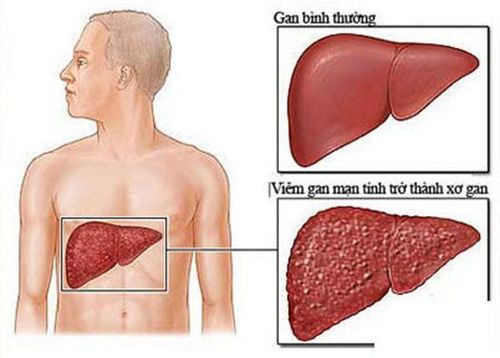

Giãn tĩnh mạch thực quản là một tình trạng bất thường khi tăng áp cửa thường gặp do xơ gan. Lúc này, các tĩnh mạch trở nên giãn lớn, tăng kích thước, nhô lên trên niêm mạc và lồi vào bên trong lòng thực quản.

Gan là một tạng có kích thước lớn, cấu trúc bên trong có chứa hệ thống tĩnh mạch cửa – hồi lưu của gần như toàn bộ hệ tĩnh mạch nội tạng trong ổ bụng, góp phần một lưu lượng khá lớn vào tĩnh mạch chủ dưới trở về tim. Theo đó, chụp số hóa xóa nền và gây tắc búi giãn tĩnh mạch thực quản qua da, cũng như mọi can thiệp khác vào gan, luôn ẩn chứa những nguy cơ sang chấn nhất định. Trong số đó, hai biến chứng thường gặp là: